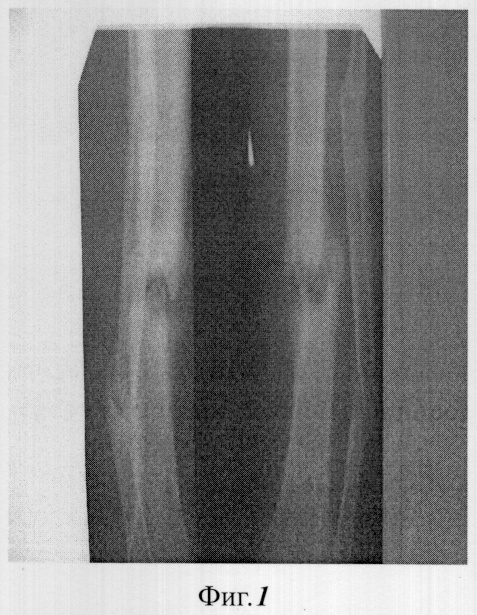

Фиг.1 – рентгенограмма ложного сустава до лечения;

Пример 1. Больной С. 21 года (история болезни №2816), инвалид 2 группы. Травму костей голени получил при выполнении служебного долга. В течение 2 лет перенес 4 операции. Сформировался дефект большеберцовой кости в форме ложного сустава (фиг.1). В зоне дефекта-псевдоартроза мягкие ткани рубцово-изменены.